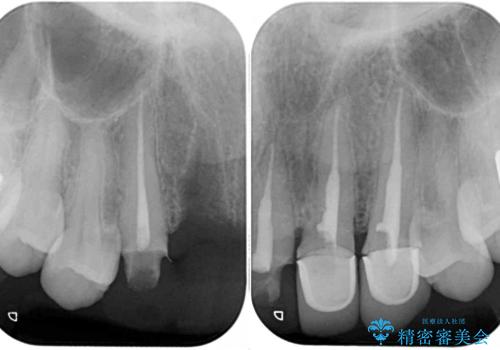

- 前歯を2本抜歯した後に装着した仮歯が長く見えるのが気になるとのことで来院された患者様です。

抜歯後には歯を支えていた骨が失われるため、歯肉が痩せてしまい、結果としてブリッジのダミーの歯を長くする必要があります。

歯肉が痩せてしまっている状態を改善するため、口蓋から歯肉の結合組織を採取し、移植することで厚みを増大させることとし、その後オールセラミックブリッジにて補綴治療を行うこととしました。